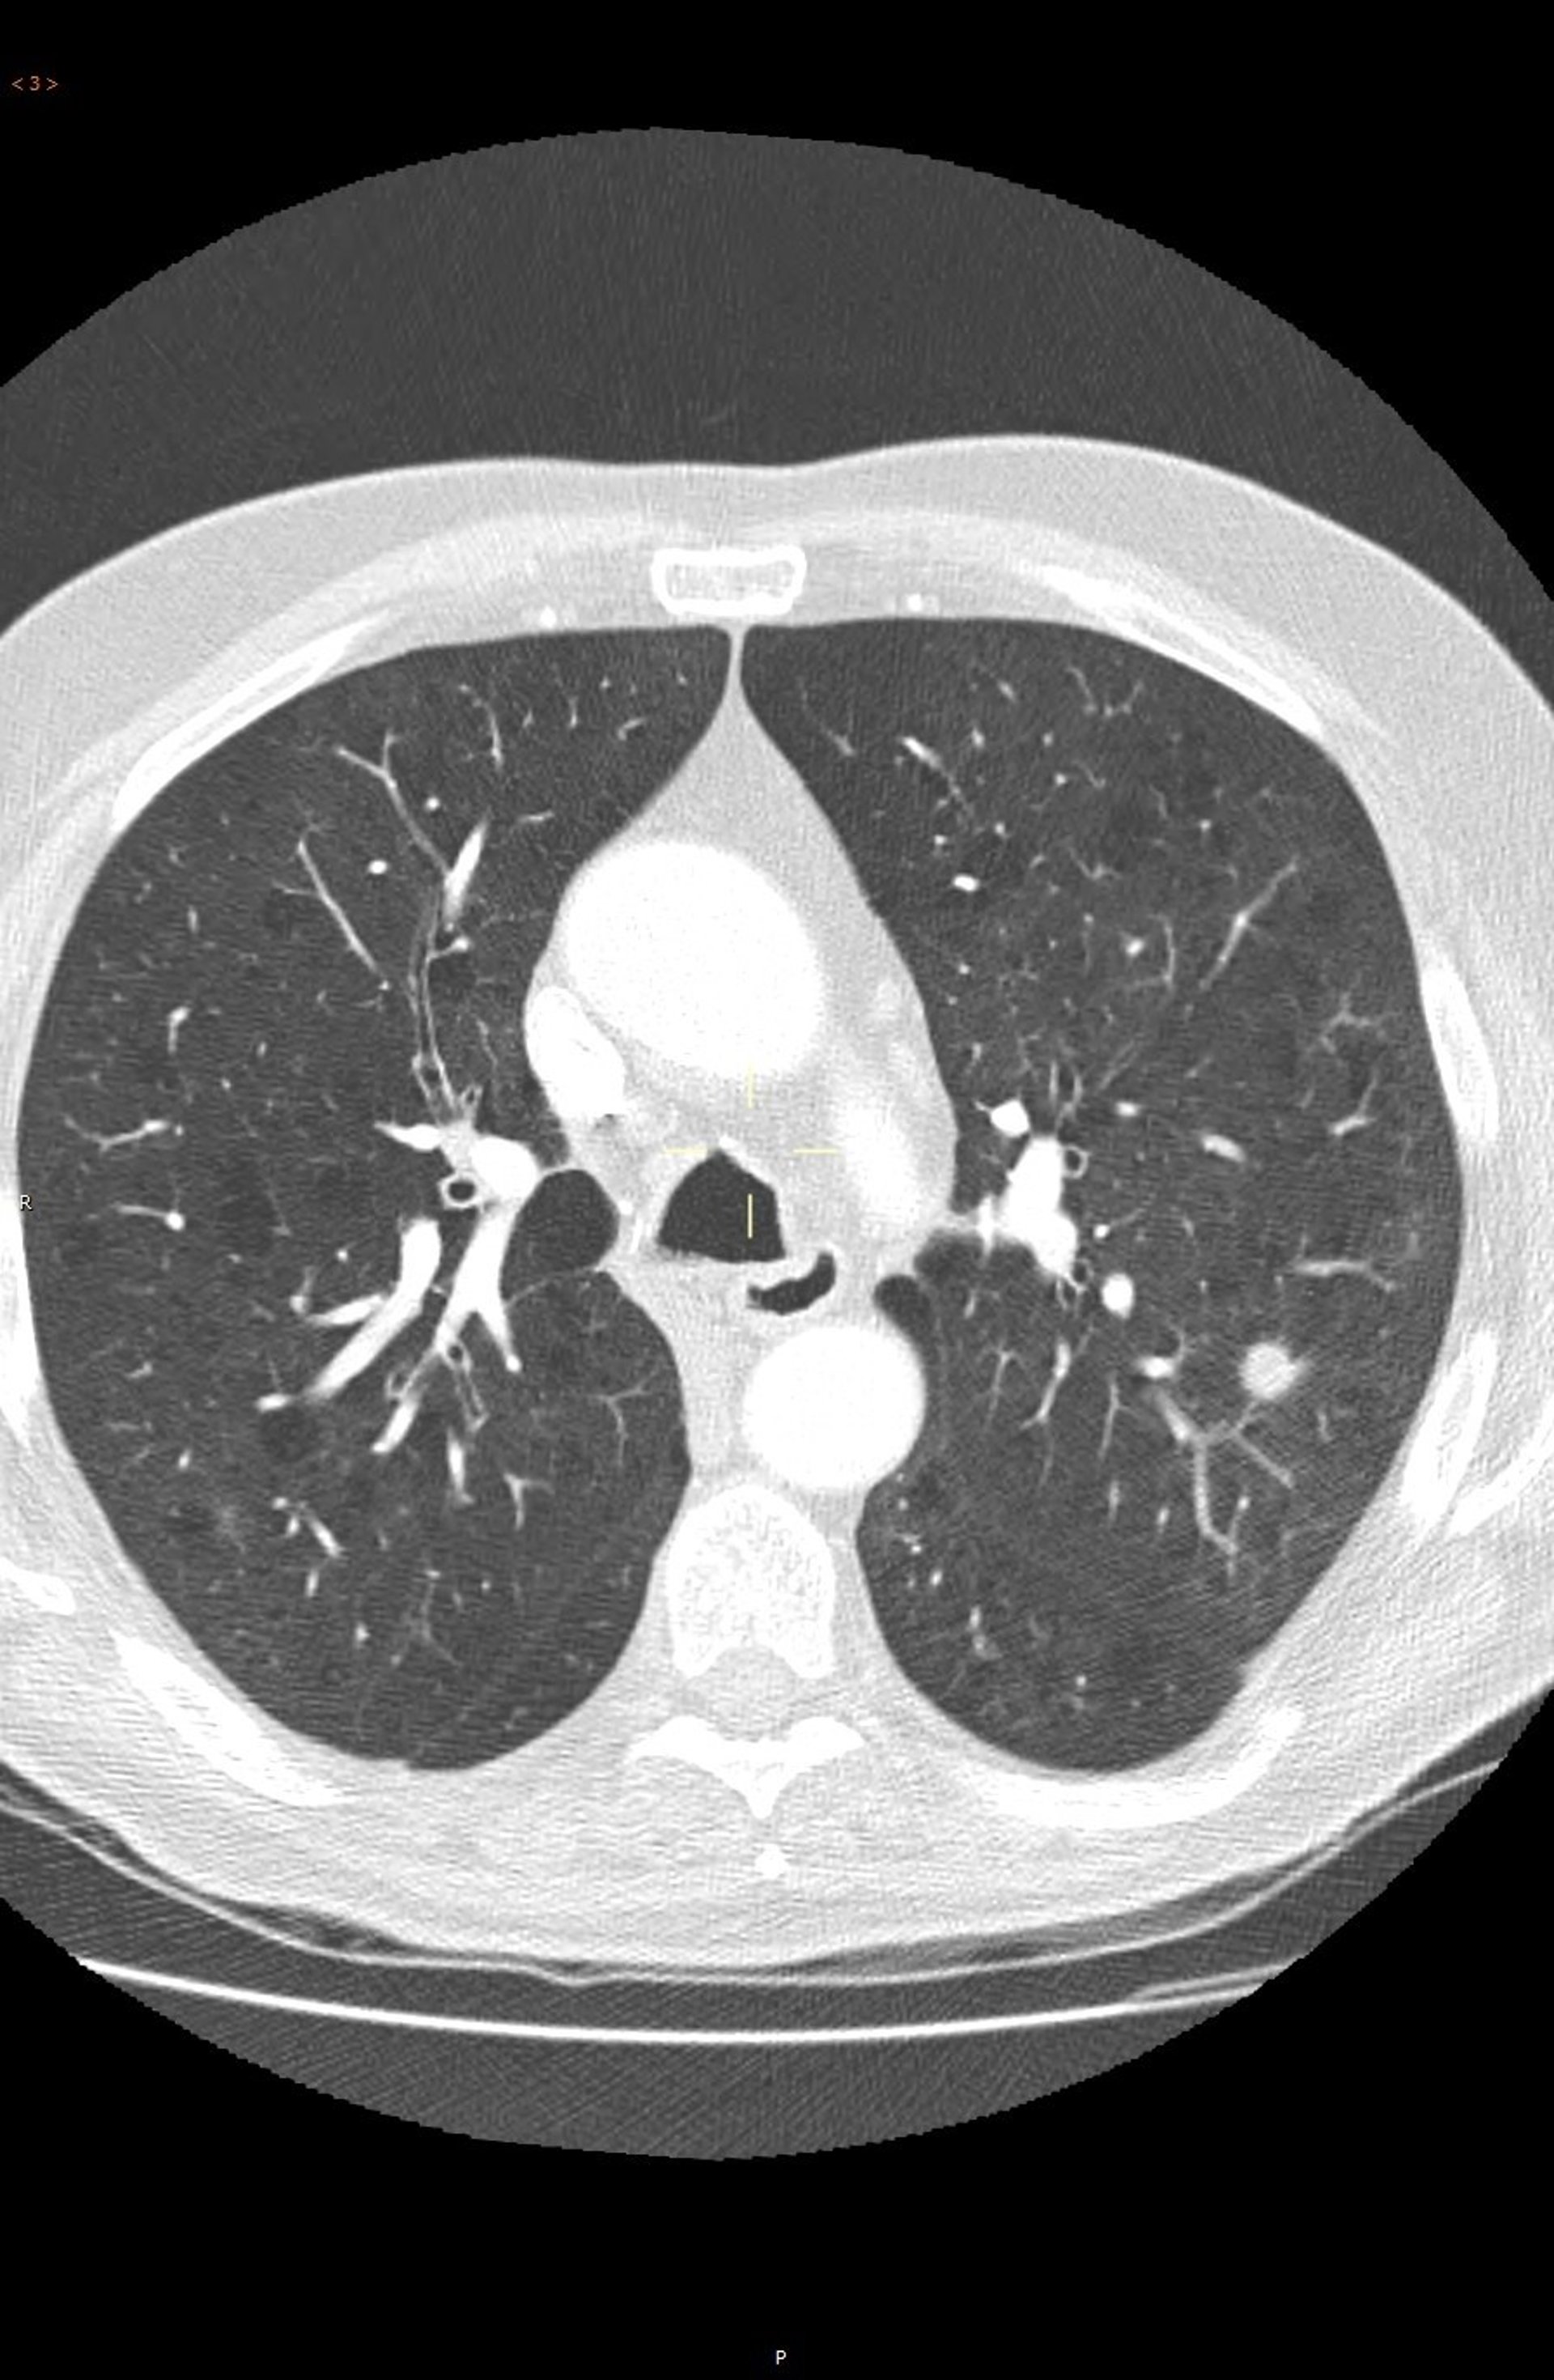

Deteccion precoz del cáncer de pulmón.

Deteccion precoz del cáncer de pulmón. - QUIRÓNSALUD - Archivo